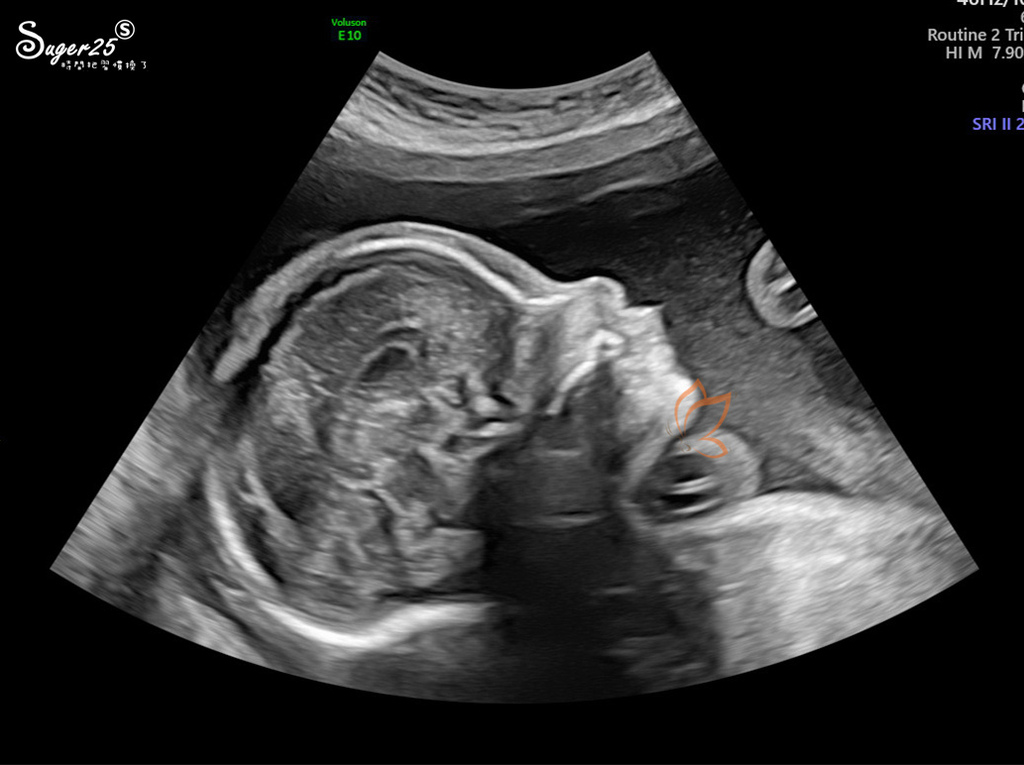

我最喜歡這張側面

感覺好清秀鼻子好像比小妞姊姊挺一點點,五官OK!健康沒有兔唇

放幾張我比較看得懂的

這張好像蒼蠅 哈哈哈哈哈 是五官

照的真的很仔細,從頭到腳,還有身體所有器官、靜脈動脈...等,左右兩邊的手跟腳

大腦小腦~子宮頸長度